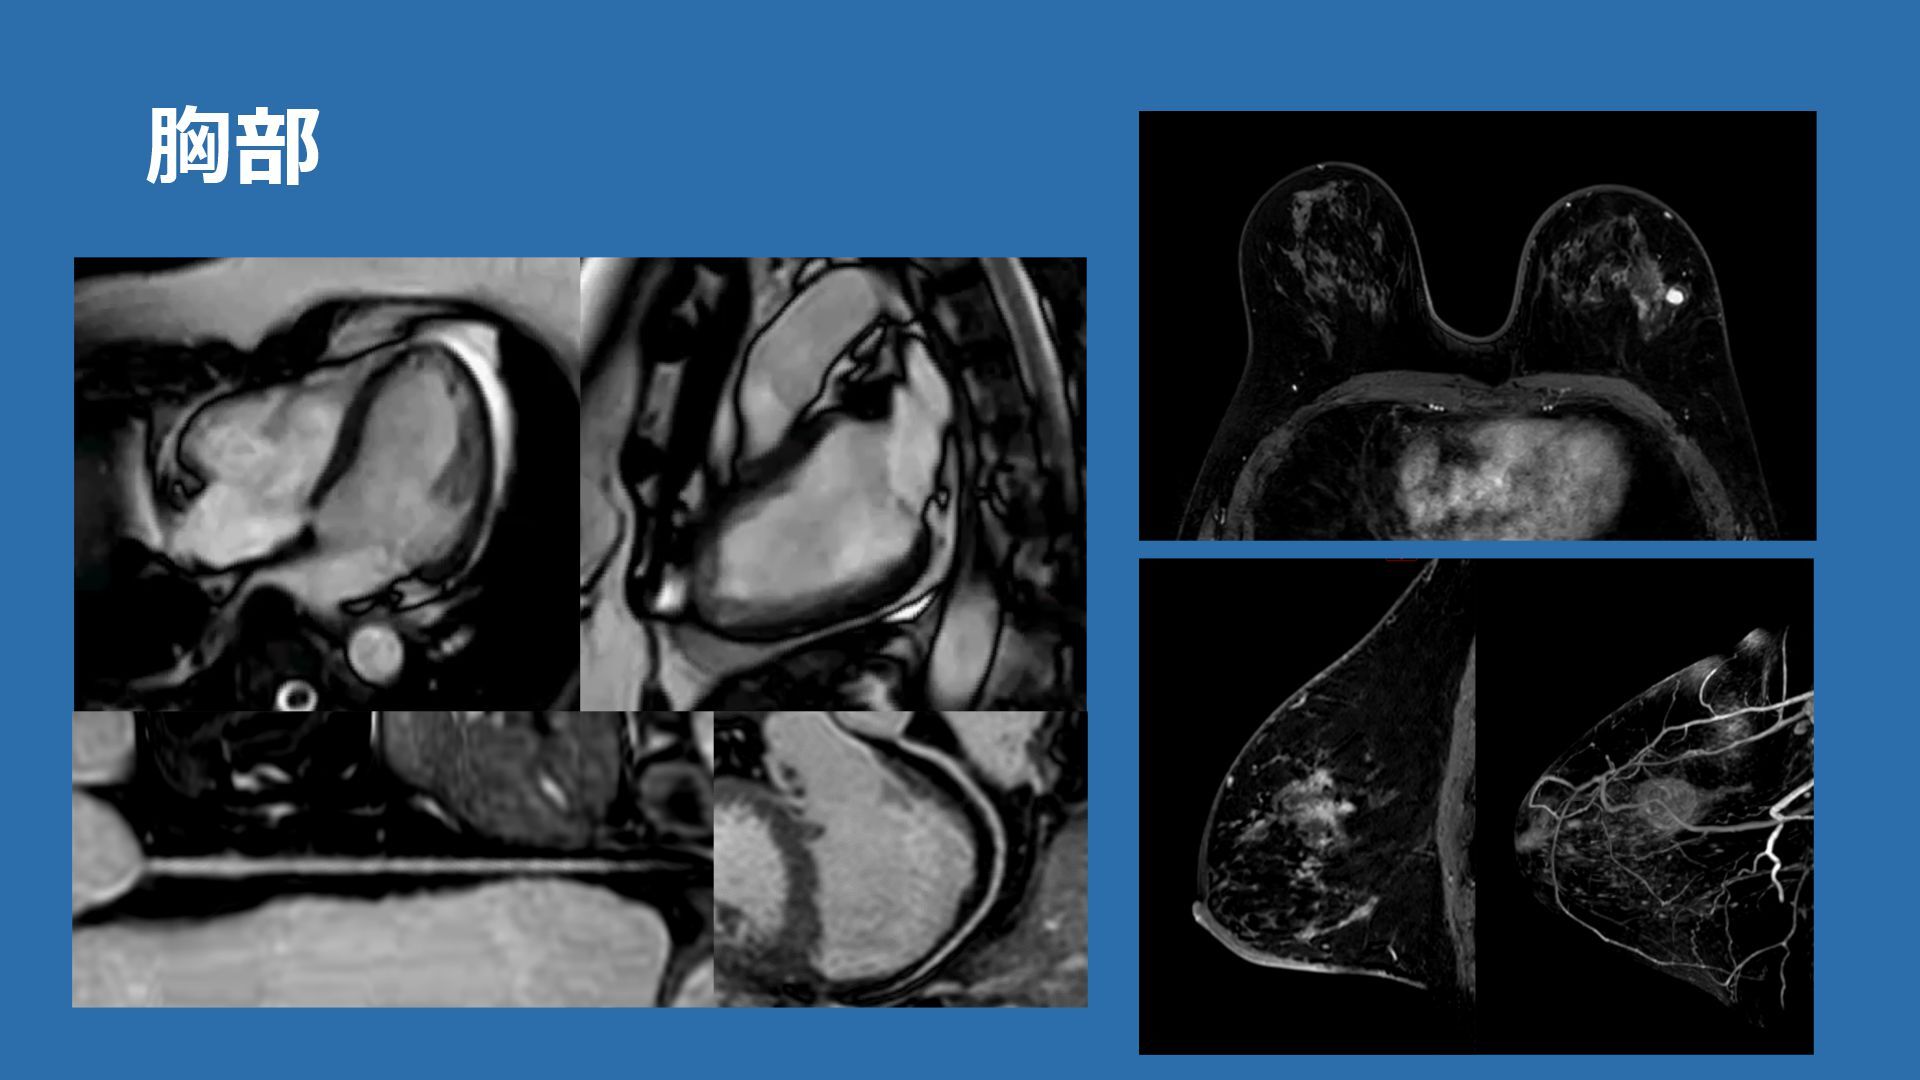

胸部